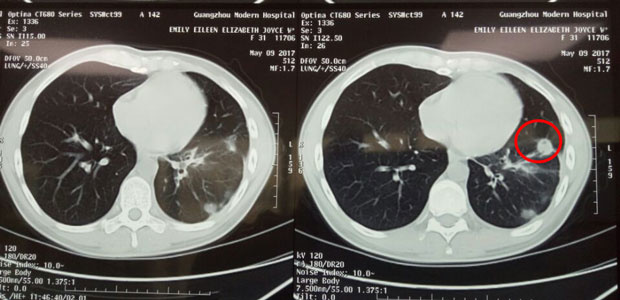

When Emily was admitted into St. Stamford Modern Cancer Hospital Guangzhou, she was very weak. She kept coughing day and night and can hardly walk or lie down. She had difficulty in breath due to the fluid in her lungs. She felt like a drowning man. After detailed check-up, doctors first helped drained out 3 liters of fluid, then interventional therapy was conducted straight away in her lung to kill the tumors. Soon after, tumors began to die off, her cough was cured and she regained her physical strength to walk all day. Emily underwent cryotherapy later, which she said was amazing and very easy. She coughed up part of the dead tumor four days after the cryotherapy. Till now, she has experienced three sessions of interventional therapy and two sessions of cryotherapy. The latest CT scan result showed that tumors in her lungs were much smaller, and the largest one already shrank by 4 cm.

In May, tumors in her lung